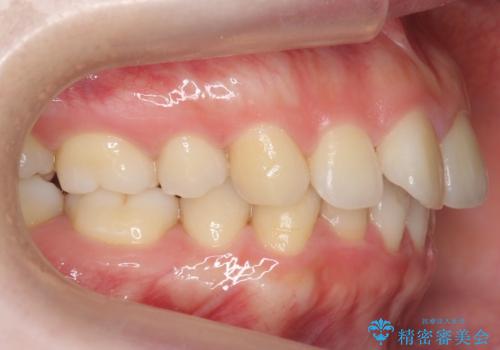

- 小さいころに小臼歯を抜歯しワイヤー矯正をしたが、すき間が空いてきて、前歯の並びが戻ってしまったとのこと。

インビザラインライトという部分矯正コースで、全体矯正に比べ、比較的安価に治療しました。

前歯の並びが格段にきれいになり、大変喜んでいただけました。